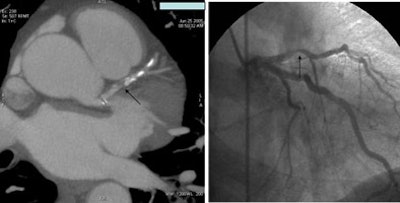

![]() |

| A 59-year-old woman presenting with chest pain had a normal CTA, as shown below right with visualization of the atrioventricular nodal branch. |